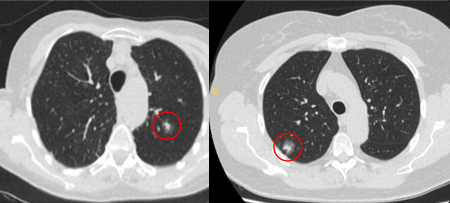

Tomografia computadorizada (TC) mostrando exemplos de nódulos perifissurais malignos. Observe a borda espiculada dos nódulos e a evidente retração da fissura adjacente. Ambas as análises de tecido de ressecção confirmaram adenocarcinoma de pulmão

Do acervo de Dr. George Tsaknis, MD, PhD, FRCP (Londres), MRQA, MAcadMEd, PGCert; usado com permissão